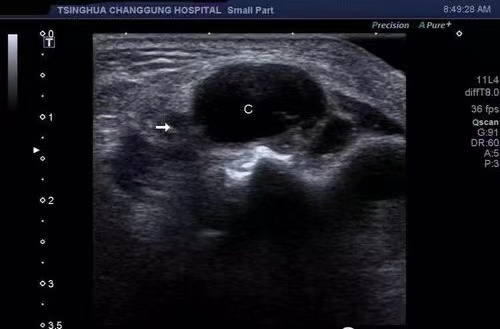

我院功能科在全市率先开展胃肠超声检查

今年1月份,我院功能科在全市率先开展胃肠超声检查新业务。截至目前胃超声共检查170余例,肠道超声检查10余例,深受广大患者好评。

胃肠超声是指患者口服助显剂充盈胃肠后,排除胃腔及肠道内气体和黏液,清晰地显示胃肠壁层次结构以及病变的超声检查方法。我院功能科副主任医师杨赟在协和医院进修学习后,掌握该项技能。

胃超声与普通胃镜的区别就是能看到胃壁里面的结构,发现胃壁肿瘤的部位、大小和形态,对粘膜下、肌壁间病变及外侵性病变有优势。胃超声与胃镜检查相辅相成,取长补短,提高了胃部疾病检查诊断的全面性和准确性。肠道超声检查可以观察到小肠、结肠及直肠的肠壁厚度、层次结构、肠腔狭窄或扩张,以及肠外的病变,成为肠道疾病的有效诊断方法。